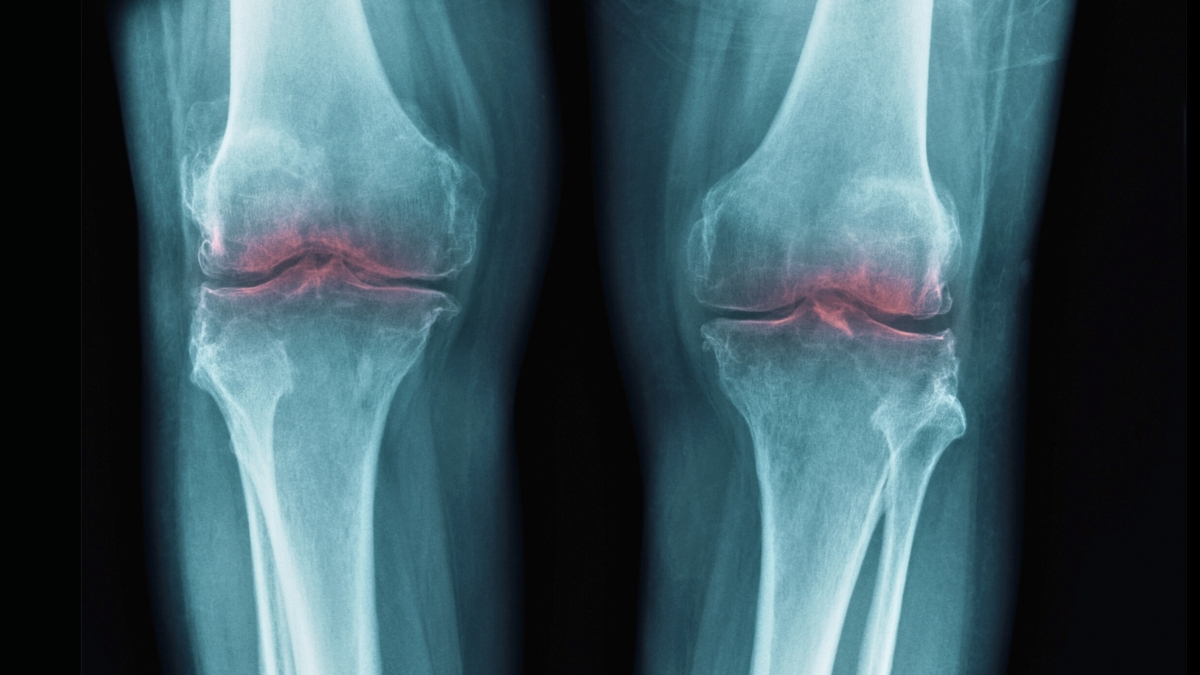

This connection has led scientists to investigate its role in osteoarthritis, a condition where joint stress contributes to collagen breakdown in cartilage, resulting in pain and inflammation.

Similar experiments were conducted using human tissue samples from knee replacement surgeries. The results showed significant regeneration, with cartilage appearing stiffer and exhibiting less inflammation.